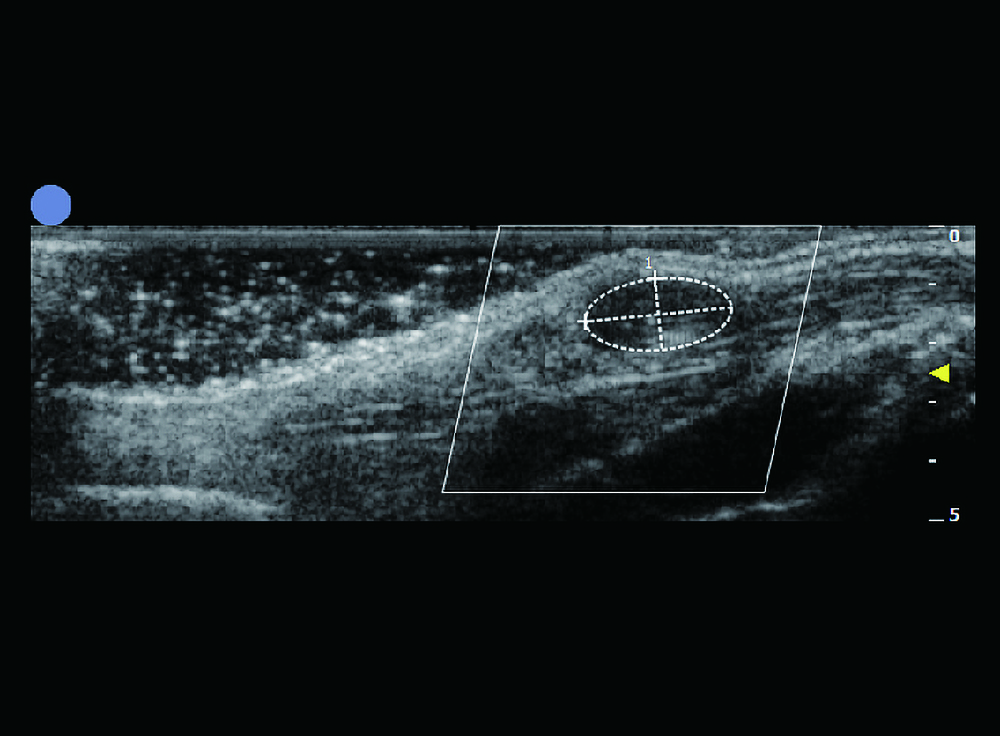

小动物B超

¥350 - 450